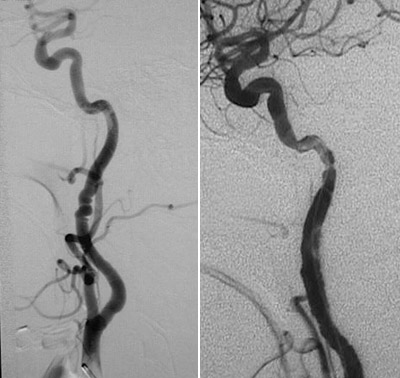

Fibromuscular dysplasia of a cerebral artery is demonstrated here with areas of

beading and narrowing

.